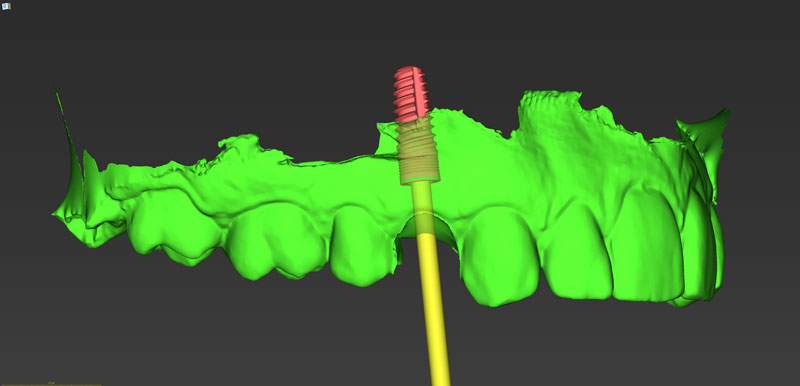

Ψηφιακό πλάνο θεραπείας

Κατευθυνόμενη τοποθέτηση εμφυτευμάτων

Είδη και ακρίβεια χειρουργικού οδηγού

Σχεδιασμός χειρουργικού οδηγού

Κατασκευή χειρουργικού οδηγού στο ιατρείο (3d printing)

- Κατευθυνόμενη τοποθέτηση εμφυτευμάτων

- Είδη και ακρίβεια χειρουργικού οδηγού

- Σχεδιασμός χειρουργικού οδηγού

- Κατασκευή χειρουργικού οδηγού στο ιατρείο (3d printing)